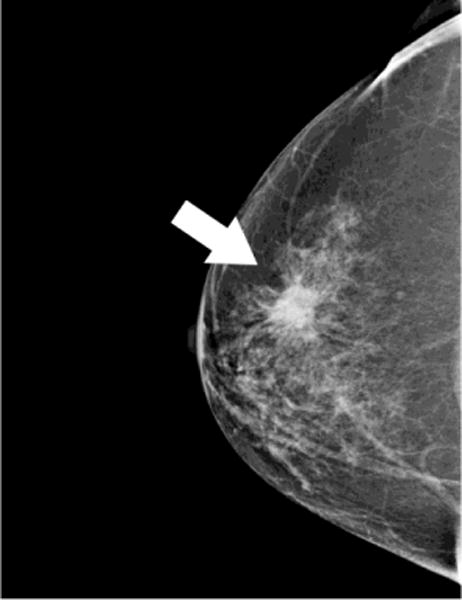

Fig. 2. Small Invasive Ductal Carcinoma.

55 year-old woman presents for screening mammogram. Mammographic CC (A) and MLO (B) views demonstrate heterogeneously dense breast tissue with ill-defined focal asymmetry in the deep right breast at the 12 o’clock position (white circles). Contrast enhanced CBCT demonstrates more clearly a subcentimeter irregular mass (crosshairs) at the 12 o’clock location (C). Lesion diagnosed as invasive ductal carcinoma at time of biopsy.